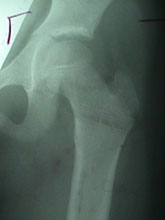

SCFE is a common hip pathology seen more frequently in boys than girls during the adolescent growth spurt. There is a mechanical weakening between the met- aphyses of the femoral neck and head causing the epiphysis to slip posteriorly.

It is more common in children with endocrine disorders, with metabolic bone disease and renal disorders. Children with bilateral slips must be evaluated for thyroid and, growth hormone deficiency and renal causes SCFE may vary from mild (early) slip to moderate and complete slip depending on the extent of displacement of epiphysis. SCFE can also be classified as Stable and Unstable slips depending on the ability of the child to bear weight on the affected leg.

Any acute, and unstable SCFE requires emergent treatment. Stable slips also need to pinned on an elective basis. Untreated or unreduced SCFE can lead to Avascular Necrosis of the epiphysis, chondrolysis and Femoral-Acetabular impingment leading to early hip arthritis. Severe Slip may required open reduction using the Anterior or Watson-Jones Approach or the Safe-Surgical Hip (GANZ) Dislocation approach.